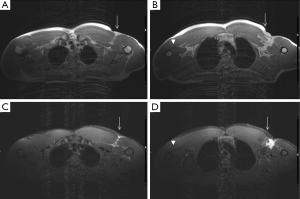

In comparison to US, MR imaging is less operator dependent, facilitates a more global assessment of the entire chest, and enables better differentiation of tendon tissue from tissues affected by trauma. It is the imaging method of choice when the diagnosis is not clear, and may avoid surgical delays particularly when surgery is indicated. Different MR imaging protocols may be suitable for imaging of thoracic wall muscles. T1-weighted sequences are good for evaluating the anatomy but lack sensitivity in the detection of fluid, with exception of some chronic hematomas due to very short T1 values (and corresponding brightness on T1-weighted images). Fluid-sensitive MR imaging sequences such as STIR, T2-weighted imaging with fat saturation, and proton-density—weighted imaging with fat saturation are essential for detecting increased fluid signal intensity induced by a traumatic process.

A normal pectoralis major tendon should have uniform low signal intensity on MR imaging. Like US (34), tears of the pectoralis major tendon seen on MR imaging exhibit different degrees of tendon abnormality, depending on the degree of injury. A grade I strain of the muscle belly will have feathery intramuscular fluid-sensitive signal intensity, which represents oedema and/or haemorrhage. Grade II injury will appear as a partial tear with an intramuscular hematoma, while grade III injury has a complete tear with possible retraction (Figures 11-13). As a matter of fact, a partial tear involving only the posterior sternal segments, the anterior clavicular head and tendon will be intact, with the long head of the biceps tendon in place. With complete tears involving both the sternal head and the clavicular head, however, there will be disruption of the entire tendon, with anterior displacement of the long head of the biceps tendon (35).